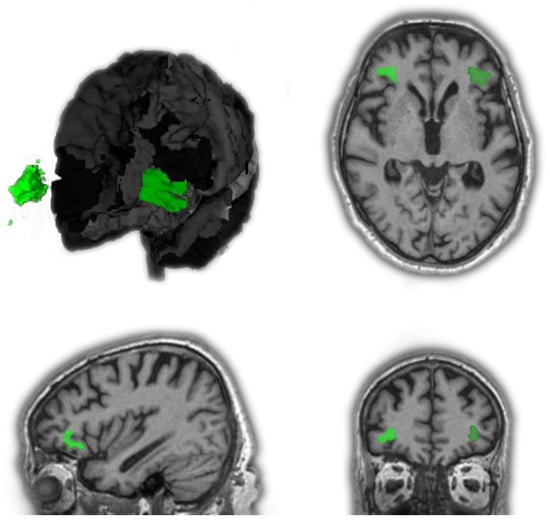

3.2.2. Patients with MCI